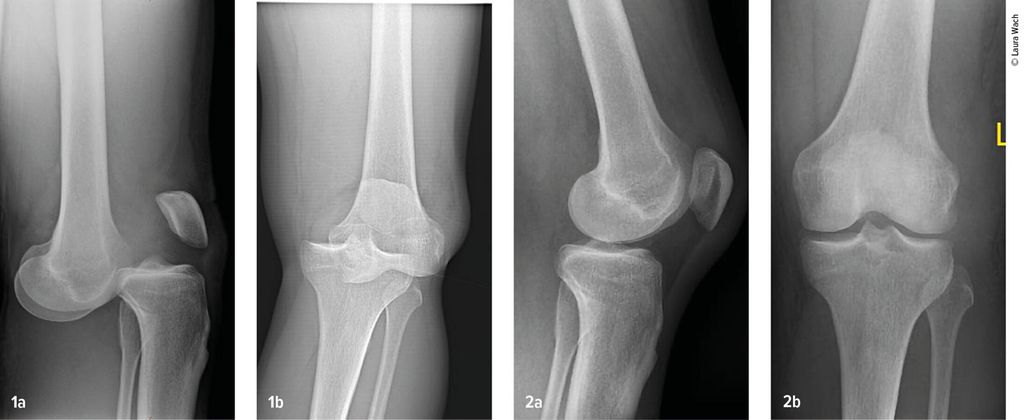

Gefäss- und Nervenverletzungen treten häufig im Zusammenhang mit einer Kniegelenkluxation auf. Henkelmann zitierte einen systematischen Review,3 der 23 Studien mit insgesamt 862 Patienten mit Kniegelenkluxationen umfasst. Bei 171 Patienten (18%) wurden Gefässverletzungen nachgewiesen. Diese kamen bei Patienten mit Schenck-Klassifikation vom Typ IIIL am häufigsten vor. Bei diesem Typ kommt es durch eine posteriore Kniegelenkluxation zur Ruptur beider Kreuzbänder und des lateralen Kollateralbandes (Abb.2 und 3). In 10 der Studien mit insgesamt 272 Patienten wurden auch Nervenverletzungen erfasst. 75 Patienten (25%) waren davon betroffen.

Abb. 1-2: Multiligamentverletzungen am jeweils linken Knie. (1) Klar ersichtlich, (2) leicht zu übersehen